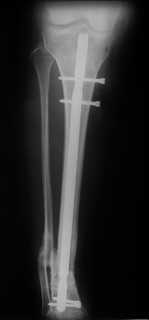

Больная оперирована.

Произвели удаление проксимальной части штифта, далее рассверлили канал до 12 мм,

Подвели и одели на конец отломка устройство с определенными техническими трудностями( проводник пришлось изогнуть, упиралось при входе в заднюю стенку, что значительно усложнило его последующее вращение, несколько раз удаляли устройство, т.к. полностью утрамбовывалось костной стружкой ) совместили отверстие на втулке и штифте и заблокировали отломком винта ( винт заранее надпилили по диаметру втулки и обломали после введения). Отломок удалился без проблем.

Заштифтовали 11 мм реконструктивным штифтом, увы, устранить деформацию полность даже поллер винтами нам не удалось. Интраоперационно на экране ЭОпа оан выглядела не так критически, как на контрольных снимках после операции. Задним умом надо было отложить штифтование после репозиции в аппарате (прав был А.Н.Челноков!), слишком были заняты идеей удаления отломка штифта не оценив проблему устранения деформации. В п/операционном периоде разрешили дозированную нагрузку на конечность.